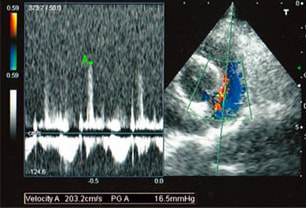

症例1:閉塞型肥大型心筋症(HOCM)【アメリカン・ショートヘア 4歳齢 去勢オス】

C:超音波写真 僧帽弁逆流と左室流出路狭窄

D:超音波写真 狭窄部の異常血流速度の測定

1年ほど前より左側胸壁からLevine 3/6の心雑音が聴取されていた。雑音の精査のため、心エコー検査を行ったところ、左室流出路の狭窄を伴う肥大型心筋症(閉塞型肥大型心筋症)と判明した。心室の拡張性を上げるため、βブロッカーであるカルベジロールを用いた治療を行っている。肥大型心筋症は犬の心疾患のように、心拡大を認めないことも多く、レントゲン写真のみで心疾患の有無を判断する事が出来ない。また、閉塞を伴わない肥大型心筋症と異なり、閉塞型の本疾患の治療に対し、Caチャネルブロッカーは推奨されない。